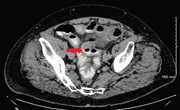

Perforated jejunal diverticulum: a rare case of acute abdomen

Rishabh Sehgal and others

Journal of Surgical Case Reports, Volume 2016, Issue 10, October 2016, rjw169, https://doi.org/10.1093/jscr/rjw169